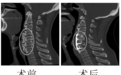

▲张伯伯喉部对比图

经过雷飞的检查,发现造成这一切的“罪魁祸首”,不是食管癌,而是颈椎前方长了一根长约7厘米、直径约2厘米的异物,压迫食道。

这异物到底是什么?雷飞介绍,耳鼻咽喉科和胸外科医生为其安排了食管造影、胃镜及颈椎三维CT等检查,异物的“身份”已经确定,医学上称之为弥漫性特发性骨肥厚症。

据了解,这是一种以韧带和肌腱钙化、骨化为特征的代谢性疾病。缺乏特征性的临床症状,多局限于影像学表现,其诊断容易被忽略,在颈部常常表现为咽喉部异物感、吞咽困难。很可能是因为颈椎的前纵韧带钙化变硬,经过数十年一点点累积,最终形成异物。该疾病具有区域差异,南方地区比较少见。